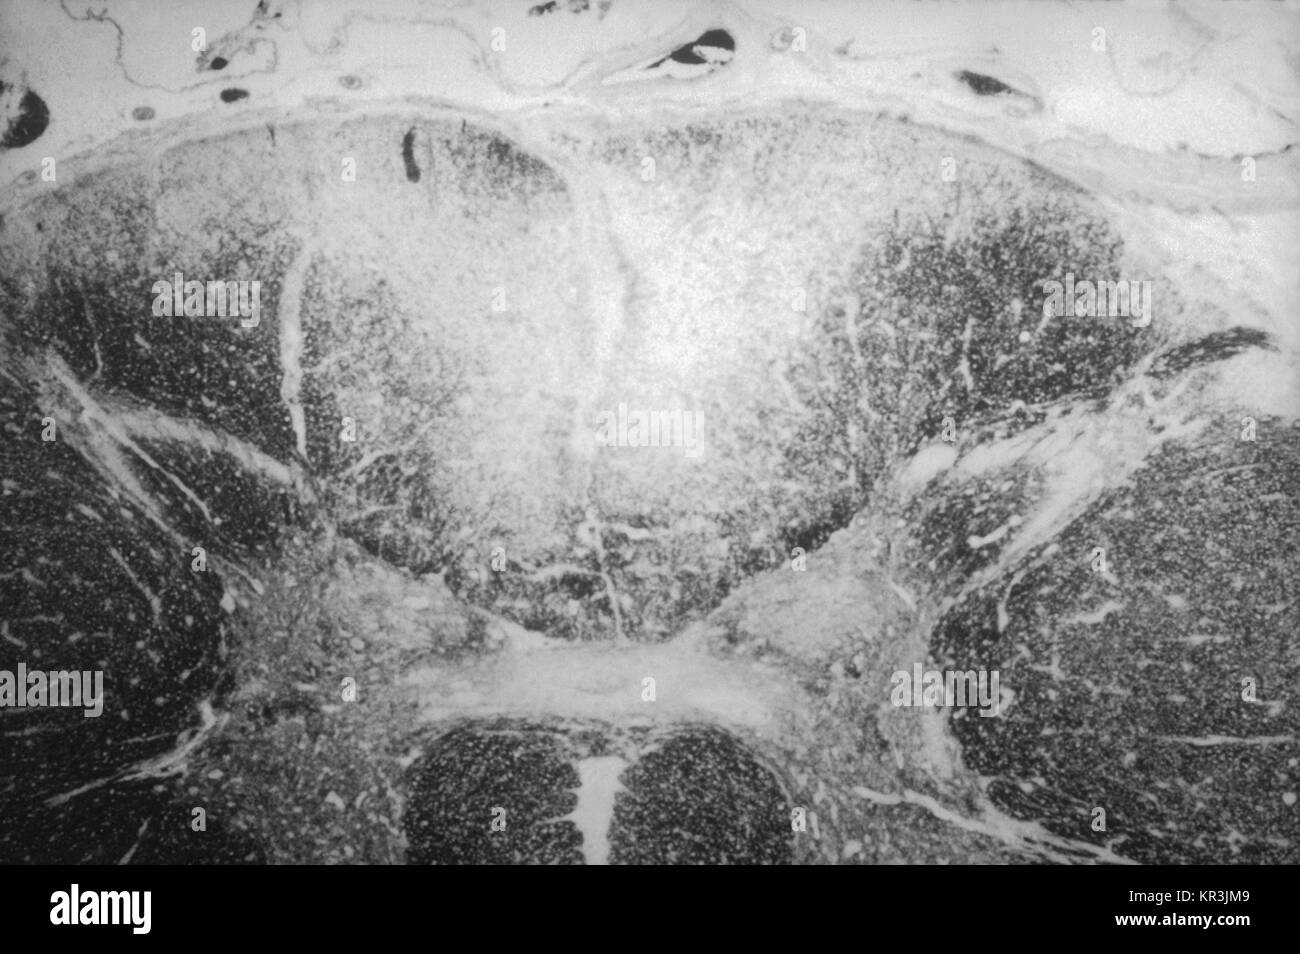

From www.alamy.de

Syphilis Medicine Stockfotos & Syphilis Medicine Bilder Seite 2 Alamy Tabes Dorsalis Syphilis Tabes dorsalis is much more common in men. tabes is characterized by gait ataxia with romberg’s sign (falling or stepping to one side when standing with feet together and eyes closed) and in most cases by argyll robertson pupils. tabes dorsalis is the result of an untreated syphilis infection. tabes dorsalis is a complication of untreated syphilis. Tabes Dorsalis Syphilis.